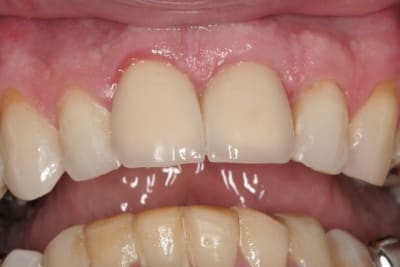

çà manque un peu de cas en ce moment...alors en voilà un ptit au passage...

11 avec résorption interne

EII avec MCI sur du dentium (4.5/14) comblement du gap vestibulaire avec du kasios tcp (très constant dans les résultats...et très économique)

pas de photos de chir par contre...j'ai du les effacer par erreur...grrrr...

la prothèse d'usage a été réalisée par ma petite associée...mais j'étais là pour superviser et faire quelques photos...;-)